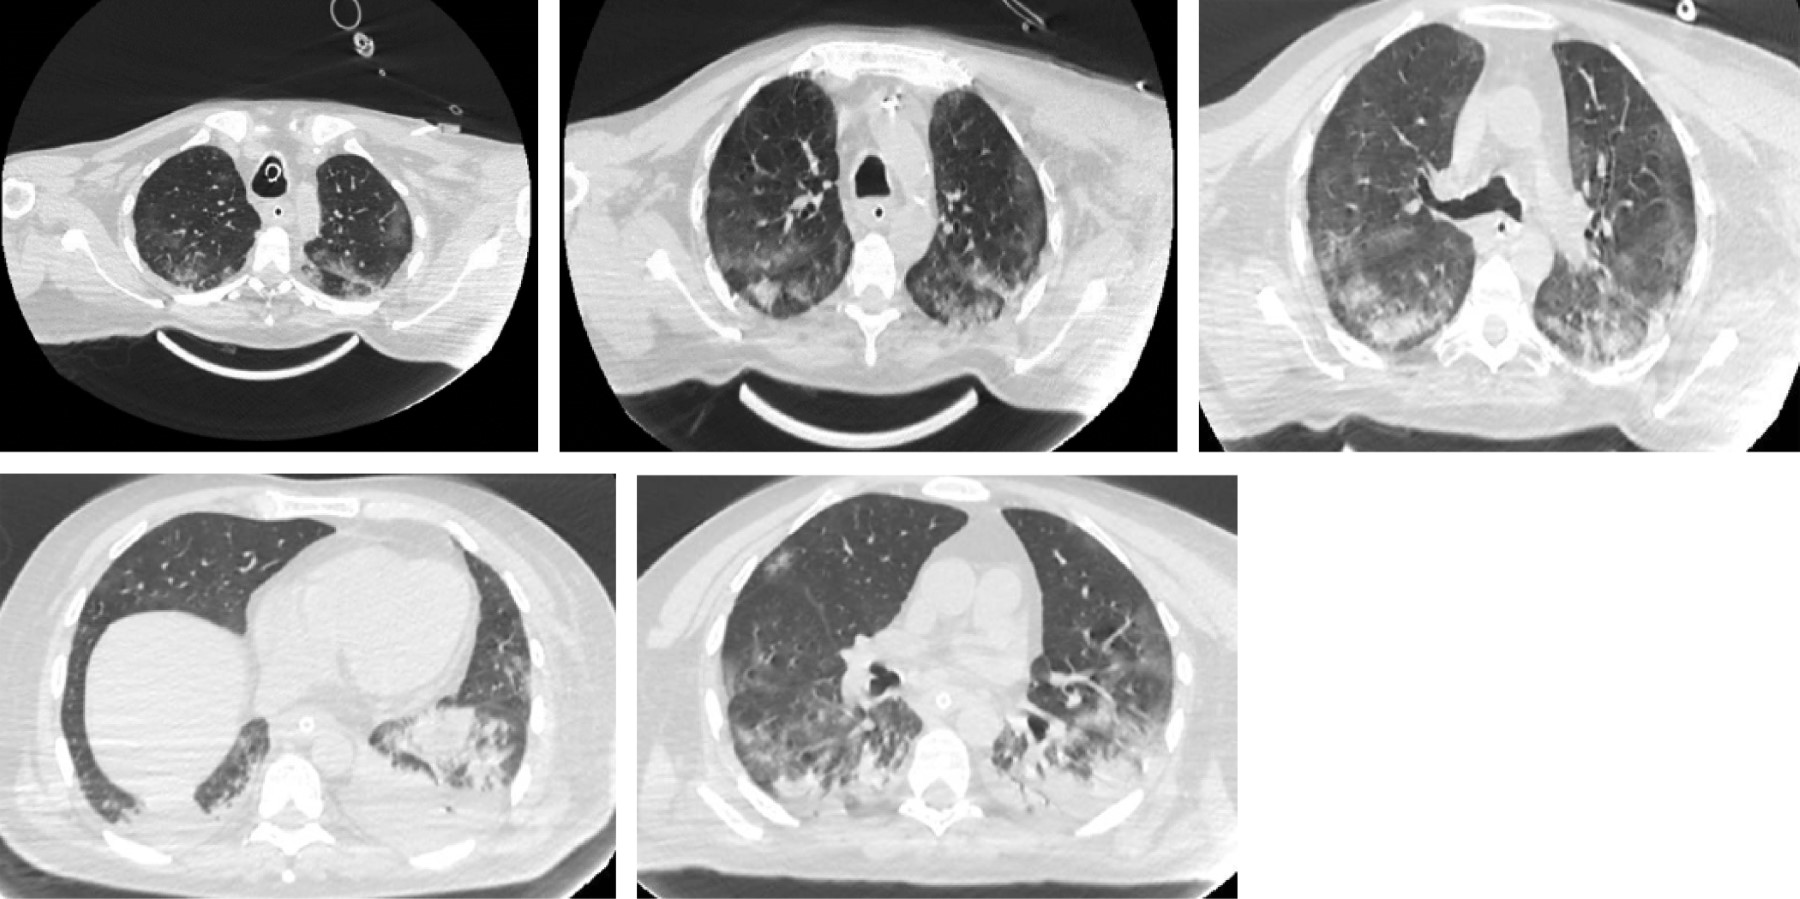

Subarachnoid hemorrhage in a patient with severe COVID-19 pneumonia, secondary to disseminated intravascular coagulation

This is a case report of a 63-year-old patient with SARS-CoV-2. Secondary to COVID-19 showing signs of severe pneumonia he is admitted to the intensive care service, requires advanced airway support and anticoagulation treatment at therapeutic doses. Derived from right hand thrombosis a tomographic study was carried out, reporting the diagnosis of Fisher 3 subarachnoid hemorrhage, the anticoagulation was suspended after 5 days, melena-type evacuations and expenditure by nasogastric tube in coffee grounds are manifested, with data of 95,000/μL thrombocytopenia, 198 mg/dL fibrinogen, INR 1.30, TTP 20.4 s, TP 12.7 s, meeting criteria of disseminated intravascular coagulation. The presentation of this case seems interesting because of the association that COVID-19 infection has to the alteration of such coagulation cascade, showing secondary bleeding.

Figure 1